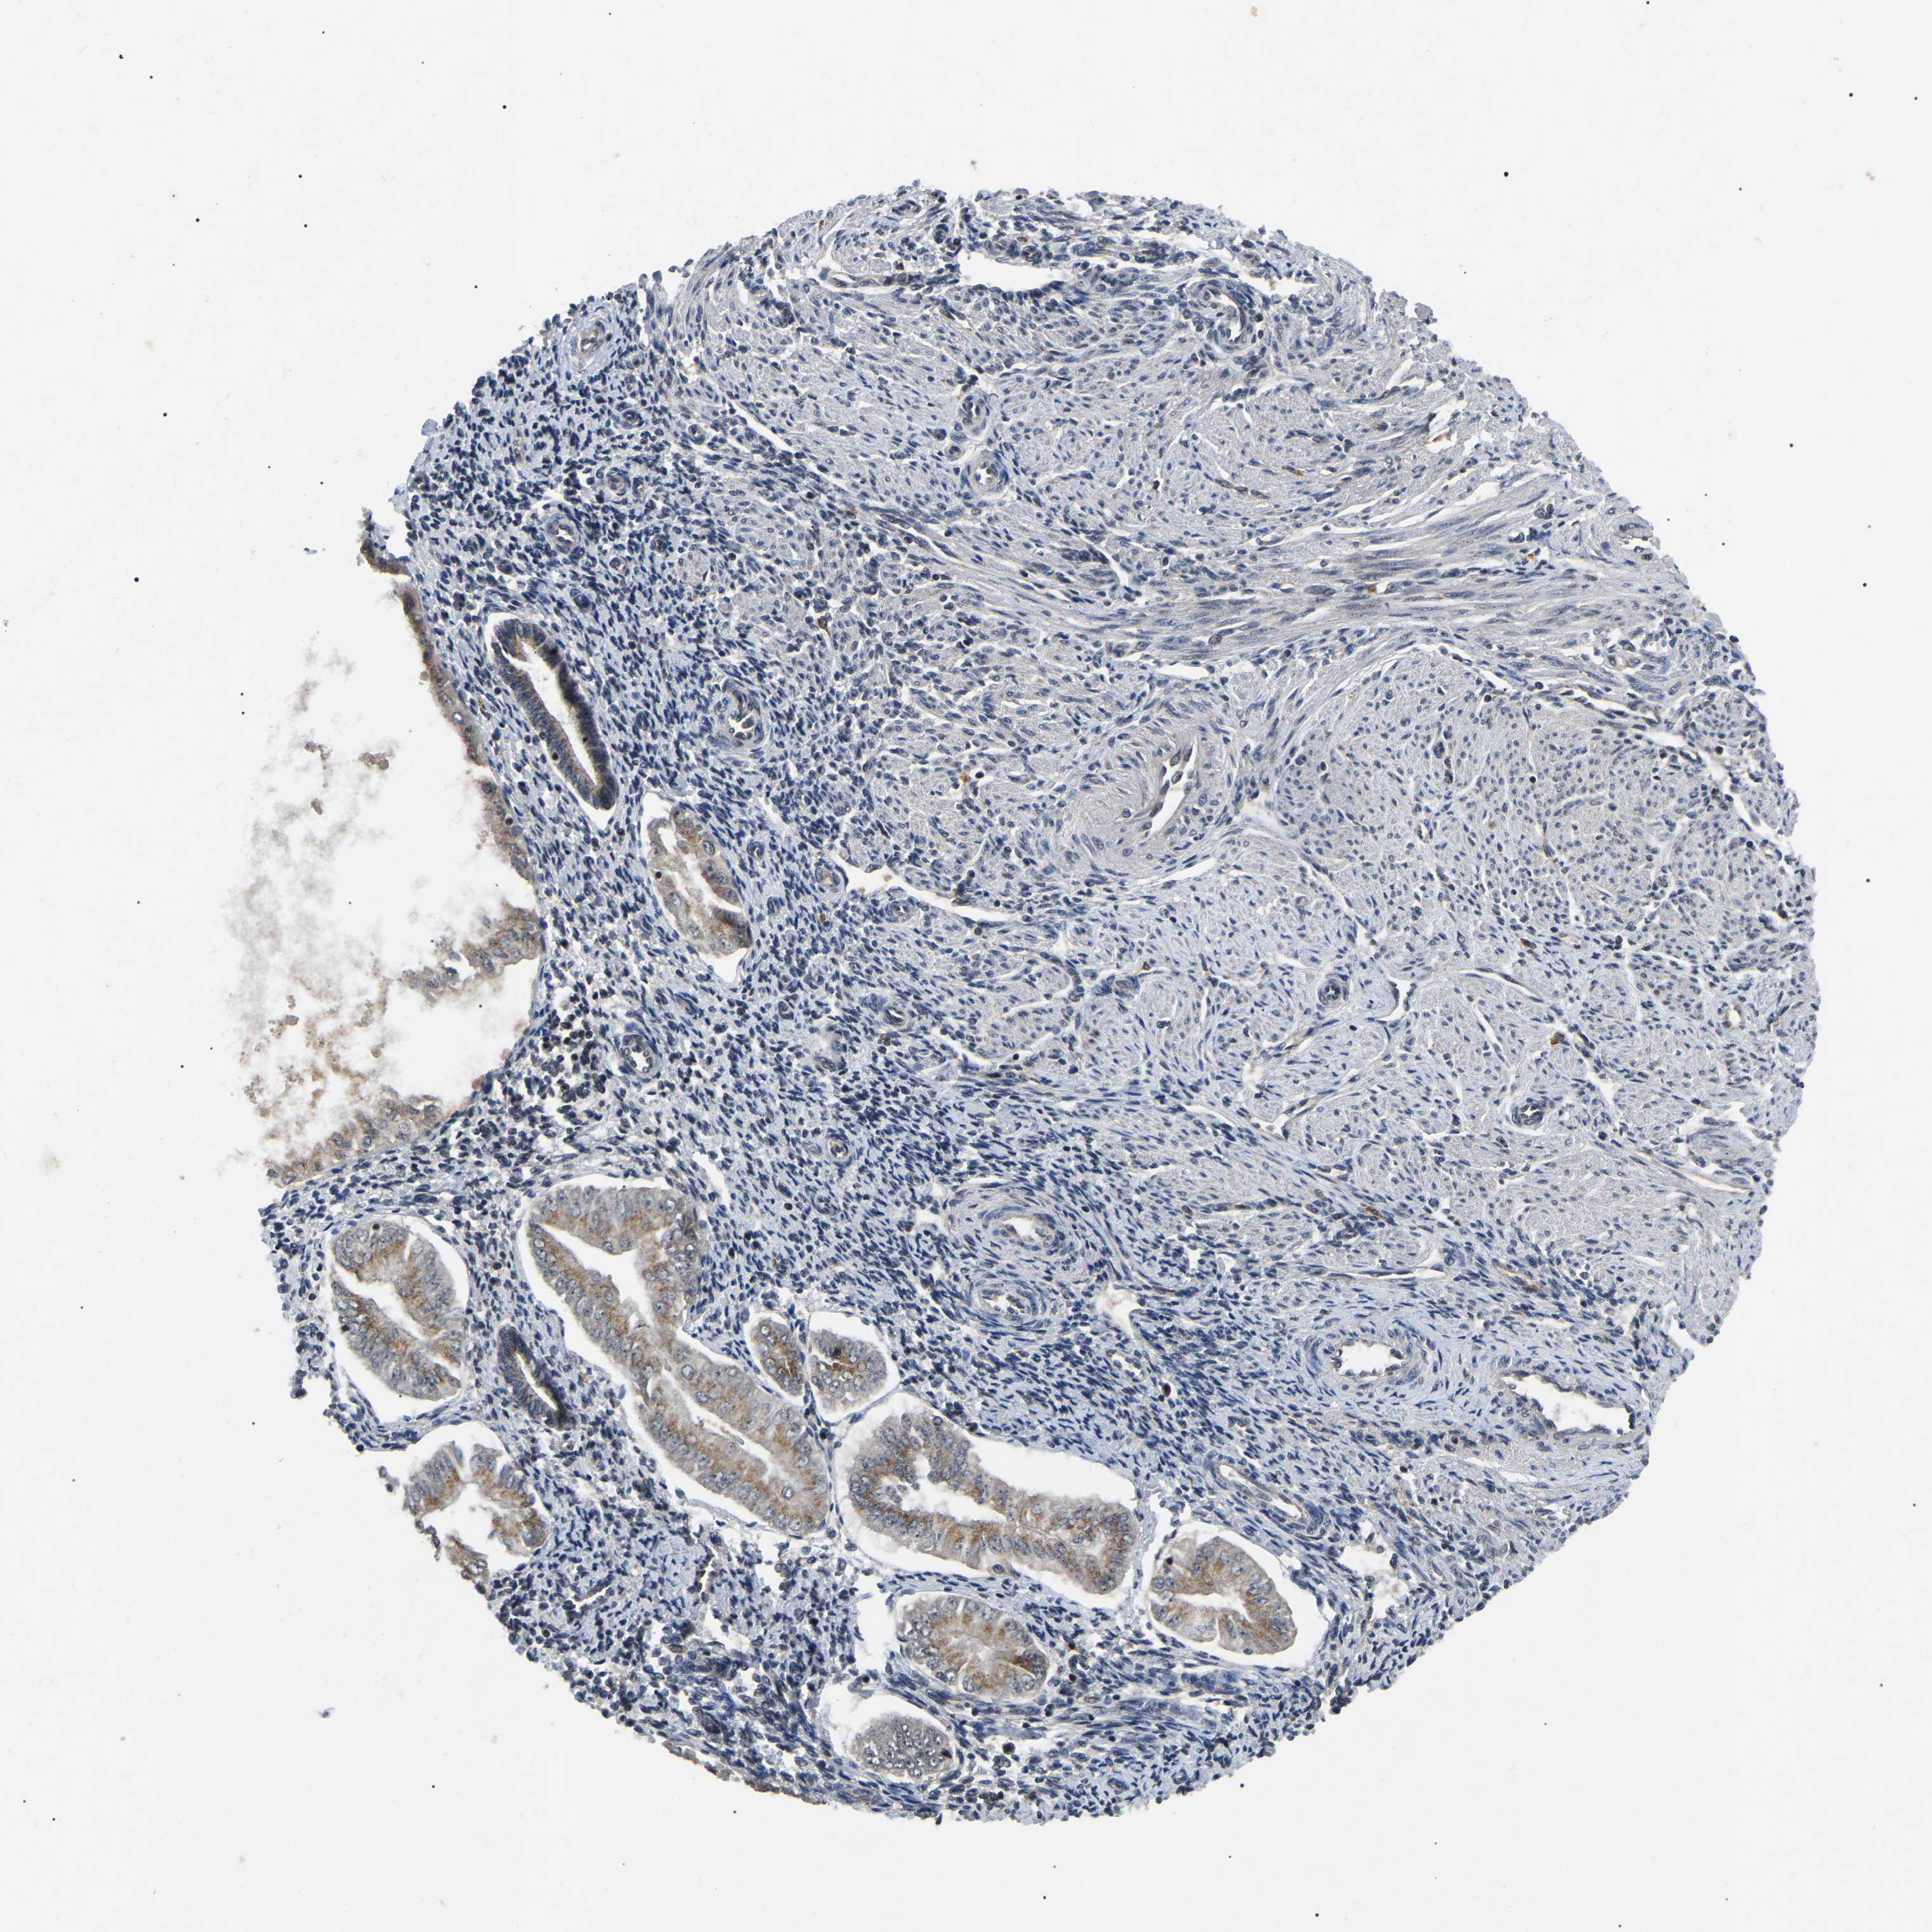

ENDOMETRIAL CANCER - Protein expressioni

A mouse-over function shows sample information and annotation data. Click on an image to view it in a full screen mode. Samples can be filtered based on level of antibody staining by selecting one or several of the following categories: high, medium, low and not detected. The assay and annotation is described here.

Note that samples used for immunohistochemistry by the Human Protein Atlas do not correspond to samples in the TCGA dataset.

Antibody stainingi

Antibody staining in the annotated cell types in the current human tissue is reported as not detected, low, medium, or high, based on conventional immunohistochemistry profiling in selected tissues. This score is based on the combination of the staining intensity and fraction of stained cells.

Each image is clickable and will lead to virtual microscopy that enables deeper exploration of all samples and also displays staining intensity scores, fraction scores and subcellular localization as well as patient and tissue information for each sample.

Antibody HPA019058

Antibody HPA026672

Staining

High

Medium

Low

Not detected

Intensity

Strong

Moderate

Weak

Negative

Quantity

>75%

75%-25%

<25%

None

Location

Nuclear

Cytoplasmic/membranous

Cytoplasmic/membranous,nuclear

Adenocarcinoma, NOS